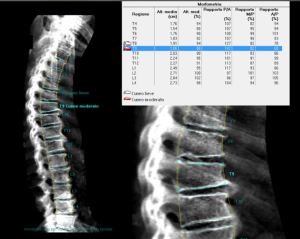

As discussed, above the increased fracture risk represents the main clinical outcome of osteoporosis. In particular, VFs represent the hallmark of osteoporosis, accounting with a prevalence of about 35% to 50% among women over 50 years of age (194). VFs frequently occur in absence of a major trauma and are often asymptomatic (195,196). Despite this, the occurrence of a VF is very important in the management of osteoporotic patients since it results in an increase in the risk of experiencing a new incident VF and other fragility fractures. Women with a pre-existing VF suffer a 4- to 5-fold increase risk of sustaining a new incident VF; this risk increases with the number of prevalent fractures at the baseline and was proved to be BMD-independent (194,197). Conventional radiography and DXA represent the techniques of choice for VFs detection (198-200). Radiologic methods for the identification and the scoring of VFs include quantitative morphometry (QM), the visual semiquantitative (SQ) method and the “algorithm-based qualitative” (ABQ) method (8). QM was introduced in order to obtain an objective and reproducible evaluation of vertebral deformities based on the measurement of vertebral body heights. QM may be performed on conventional lateral spinal radiographs or on lateral spine views acquired by DXA; the densitometric approach is commonly termed as vertebral fracture assessment (VFA) (Figure 5) (201). Typically, the center of the superior and the inferior end plates and the corner points of each vertebra from T4 to L4 are identified and then these six points are used to calculate the anterior, the middle and the posterior heights (Ha, Hm and Hp, respectively) of each vertebra and the three height ratios (Ha/Hp for wedge fracture; Hm/Hp for biconcavity fractures; ratio between Hp of adjacent vertebrae for compression fractures) (Figure 6) (38). Today, the six points placement is performed automatically with the use of a dedicated computer-assisted system to avoid inter observer variability, but manual corrections are possible at any time during the post processing of the digital images (202). Point placement may be challenging due to normal variation in the shape of vertebral bodies and projection variations; moreover, QM does not allow to distinguish between real VFs and vertebral deformities (e.g., Scheuermann’s disease, Schmorl’s node, Cupid’s bow deformity, etc.) (38,203). Unfortunately, at the current state of investigation, there is no gold standard for the definition of VFs and the exact degree of deformity that constitutes a fracture is still a matter of debate (203,204). In clinical trials, prevalent VFs are typically defined as a reduction of 3 SD or more (below the normative reference values for that particular vertebra) in any of the ratios of anterior, middle and posterior heights. In serial radiographs an incident fracture (i.e., a new VF) is defined both as an absolute change in vertebral height of at least 4 mm or as a percentage of reduction (15% or 20% reduction, depending on different studies) in the anterior, middle, or posterior heights from the baseline measurements (203,205).

The predominant approach for diagnosis of VFs is represented by the visual SQ method proposed by Genant et al. (206). On lateral spine images, VFs are identified on the basis of the apparent degree of vertebral height loss (anterior, middle and/or posterior height) and/or projected area reduction estimated by visual inspection, without direct measurements (204,206). Vertebrae from T4 to L4 are graded as normal/not fractured (grade 0), mildly deformed (grade 1: 20–25% reduction in height; 10–20% reduction of projected vertebral area), moderately deformed (grade 2: 25–40% reduction in height and 20–40% reduction of projected vertebral area) and severely deformed (grade 3: >40% reduction in any height and projected vertebral area) (206). However over time, the area reduction requirement was excluded from the examination (205). Since a linear relationship exists between the number and severity of prevalent VFs and the risk of future VFs, a spinal deformity index (SDI) can be derived from this scoring system, resulting from the sum of all grades assigned to the vertebrae divided by the number of evaluated vertebrae (38,197). The SQ method has been extensively validated and according to the ISCD official positions it represents the technique of choice for diagnosing VFs with VFA (207,208,209). Its major strength relies on the visual approach that, in experienced hands, allows to discriminate fractures from non-fracture deformities (208,209). However, a critical point of this method is represented by the accurate estimation of vertebral height reduction, especially when the degree of this reduction is close to the thresholds of the grading system (204). In light of the above issues, we believe that an integrated approach may be preferable for defining and reporting VFs. In particular, the use of QM should be encouraged to objectively graduate VFs, previously identified by the SQ method, in epidemiological studies and follow up evaluations (202).